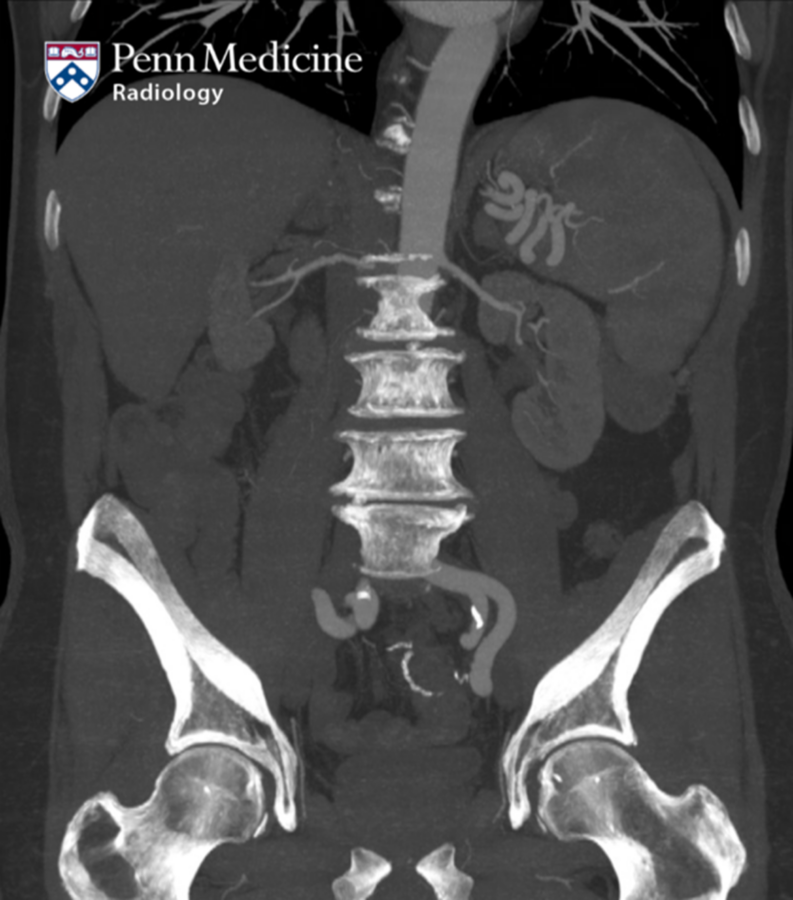

A 56-year-old man with history of coronary artery disease, myocardial infarct, hypertension, hyperlipidemia, and heart failure presented to the emergency department for painful swelling of his scrotum for a week with generalized myalgias, fatigue, and dysphonia, with the development of a large lymph node in the left supraclavicular region.